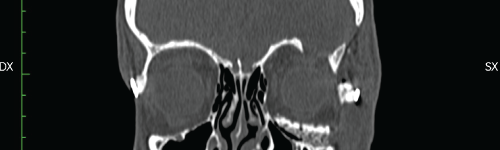

The patient's anatomy was then assessed in multiplanar (axial, coronal, sagittal) and 3D computed tomography via Toshiba Aquilon One Helical CT scanner (Figure 2), gantry = 0, slice = 1mm. The orbital floor malposition on the left side was, as measured through the CT images, 7.4 mm caudal than the contralateral one (Figure 3), causing ocular dystopia. DICOM files were processed by DeVIDE software to a .stl file. Then Netfabb software was used to obtain an ABS polymeric stereolithographic model via HP Designjet 3D printer (Figure 4). A silicon impression material was manually adapted on the stereolithopraphic model defective orbital floor to achieve a steam sterilizable autoclavable mould as a helping device in manual bone graft modelling during the surgery.